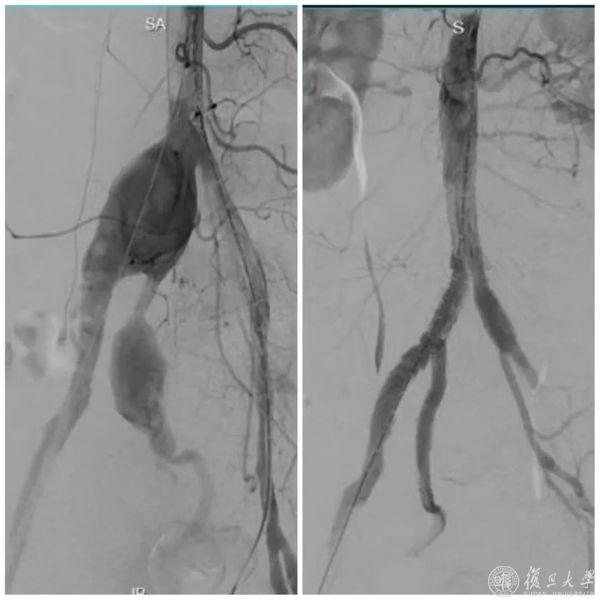

“传统的开放性人工血管置换手术创伤巨大,并发症多。”上海市公共卫生临床中心介入科周粟主任团队接诊后,决定采用微创的腹主动脉腔内修复术(EVAR)搭配髂动脉分支支架(IBD)技术精准“拆弹”。

在时长2小时的手术中,团队精准释放髂动脉分支支架与腹主动脉覆膜支架,在隔绝髂总、髂内动脉瘤及髂外动脉夹层的同时,成功将分支支架延伸入右侧髂内动脉远端分支,保障重要血流不中断。术后次日汪先生就能下床活动,并在不久后康复出院。

动脉瘤腔内修复术前后造影

复查显示,支架位置精准,瘤体和夹层被有效隔绝,髂内动脉血流通畅无渗漏。手术不但为汪先生消除了致命风险,而且从根源上预防了因髂内动脉闭塞导致的臀部缺血性疼痛、跛行、坏死以及性功能障碍等问题。